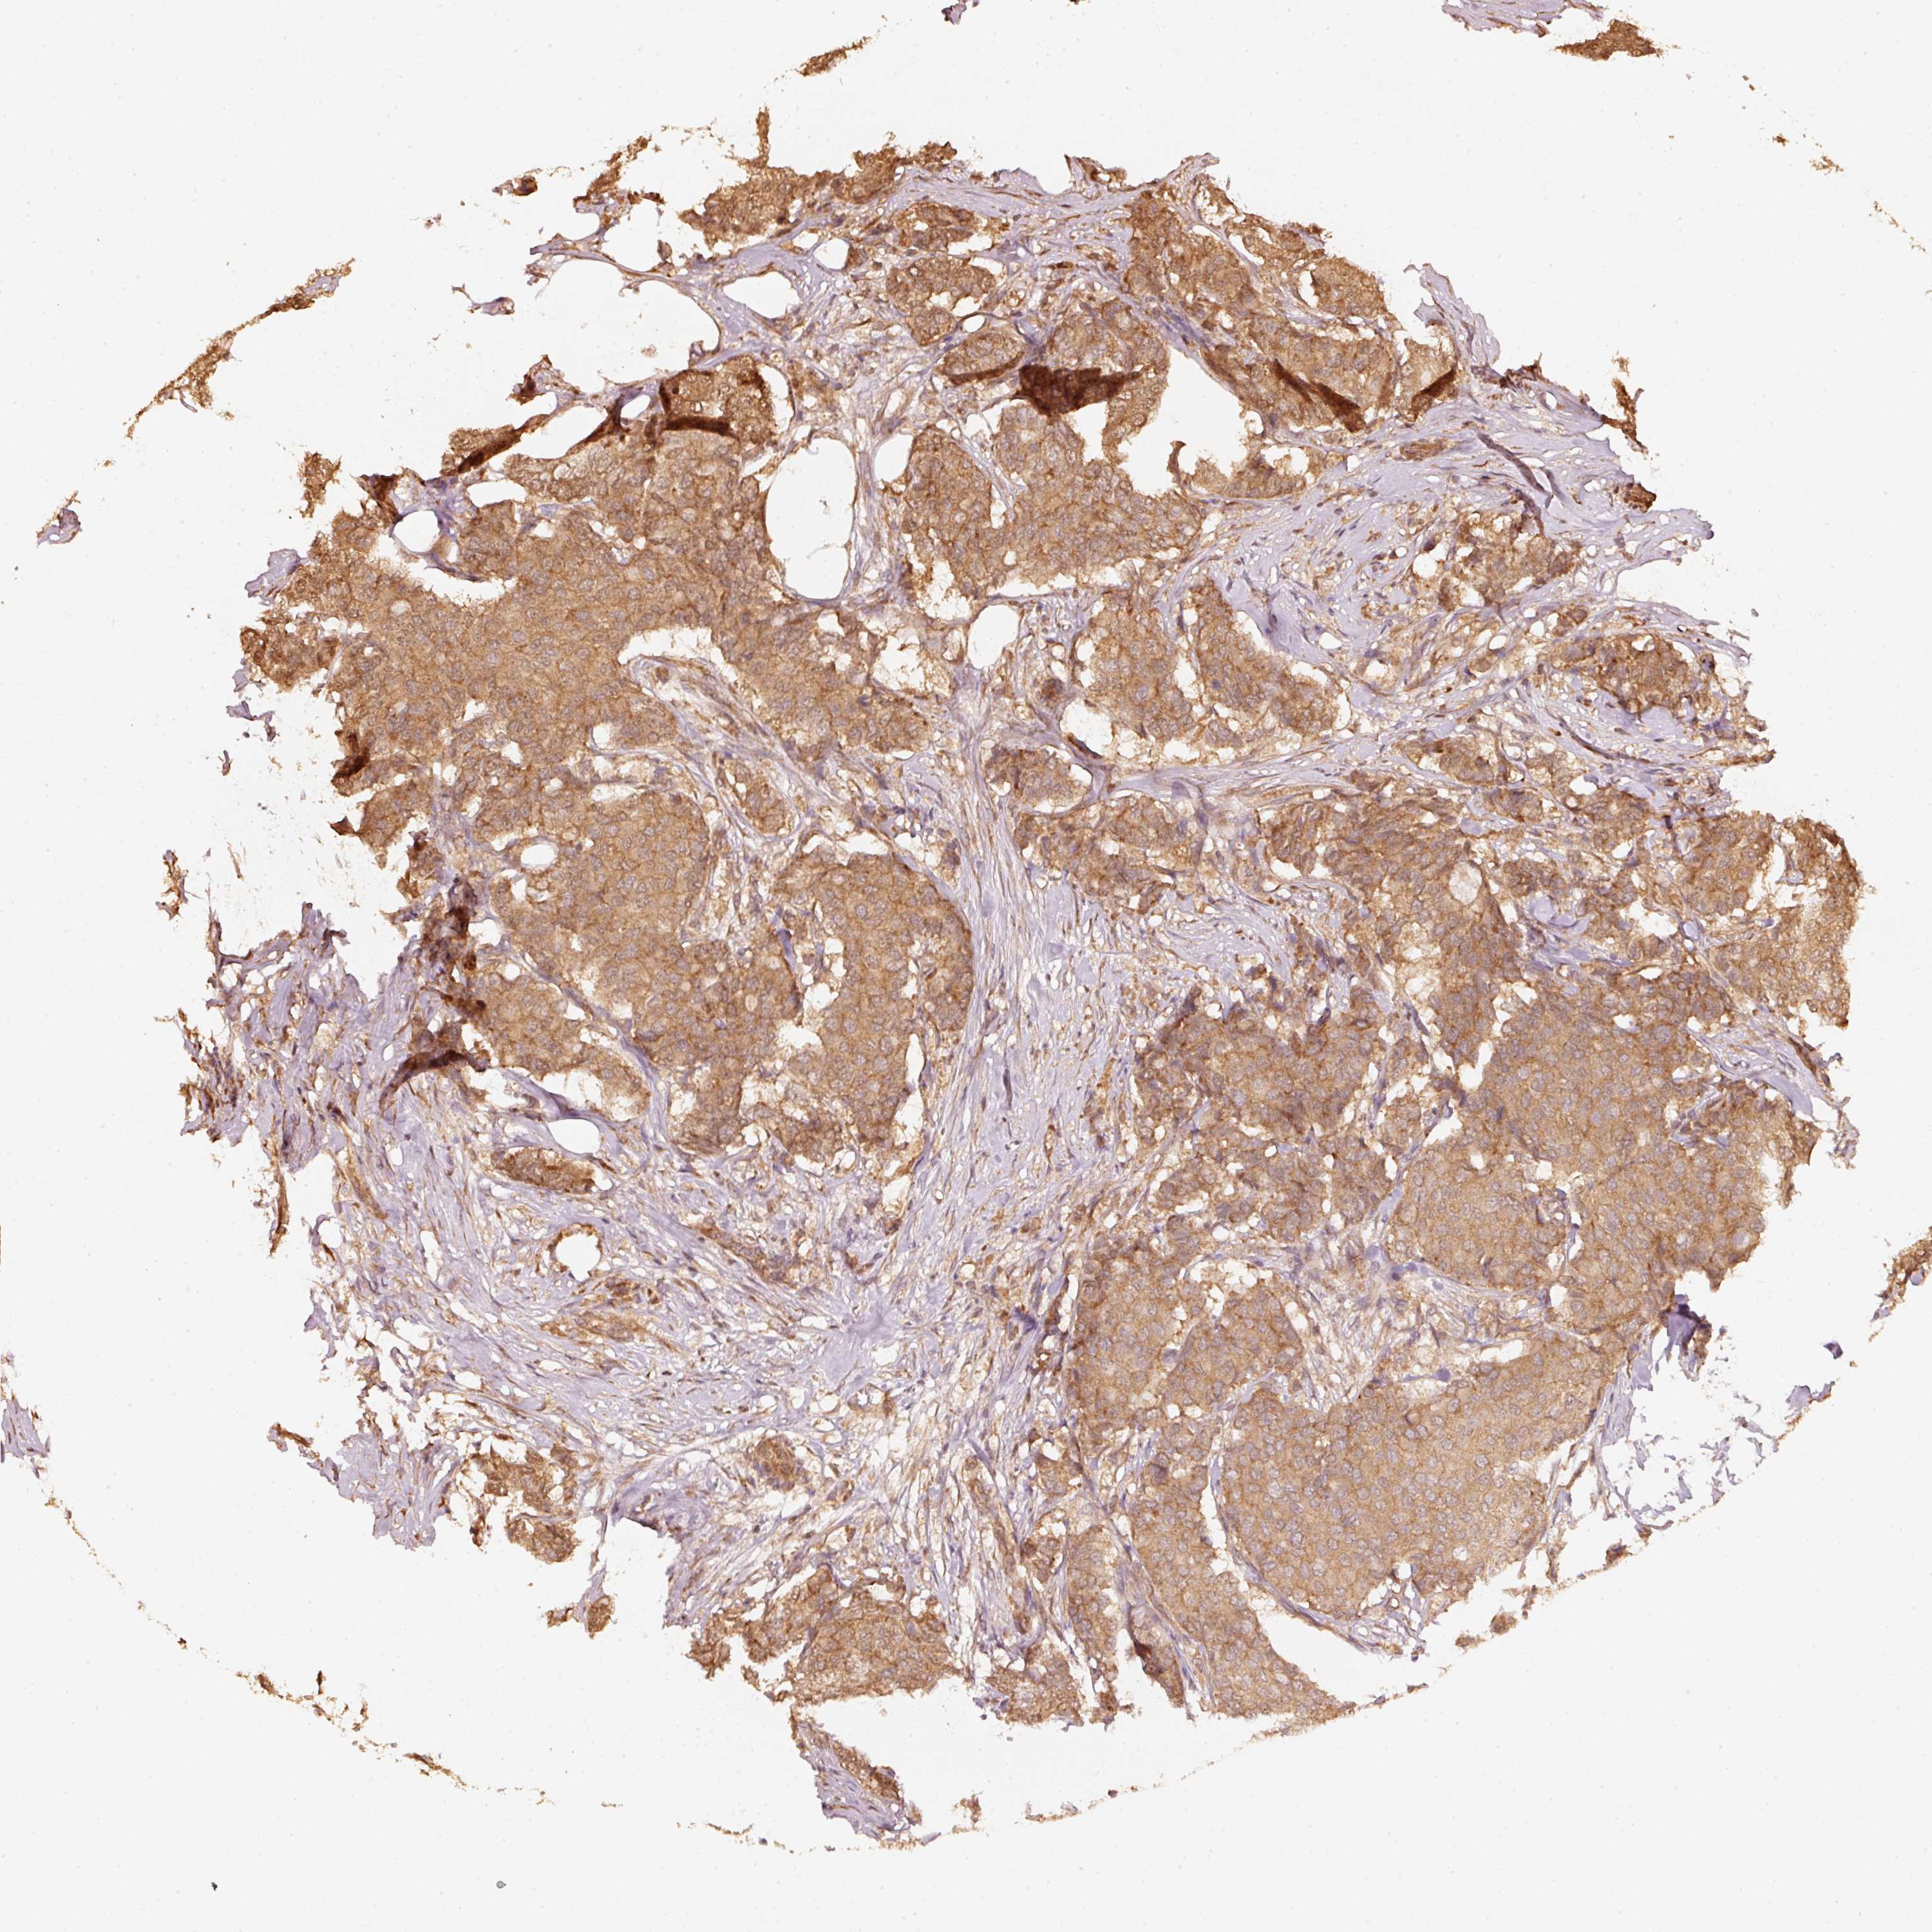

BRCA TCGA BRCA VALIDATION PROTEIN EXPRESSION

ANTIBODIES

AND

VALIDATION